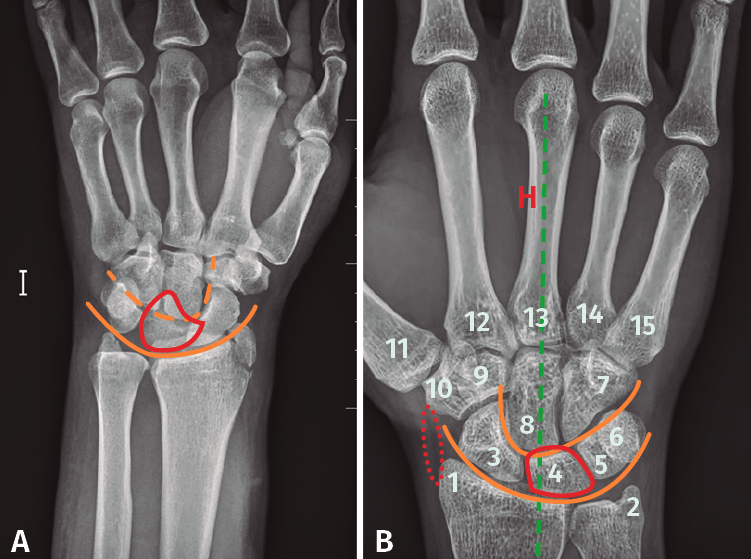

Figura 4. A: radiografía anteroposterior de luxación transestiloperilunar; B: radiografía anteroposterior sin alteraciones, recuerdo anatómico. 1: estiloides radial; 2: estiloides cubital; 3: escafoides; 4: semilunar; 5: piramidal; 6: pisiforme; 7: ganchoso; 8: grande; 9: trapecio; 10: trapezoide; 11: primer metacarpiano; 12-15: segundo a quinto metacarpianos; —: almohadilla grasa; —: eje longitudinal 3.er radio, muñeca y antebrazo; —: arcos de Gilula.

- Qué ver en una radiografía anteroposterior de muñeca (Figuras 4A y 4B). Para valorar que estamos ante una correcta proyección, debemos obtener:

En la radiografía podemos observar los siguientes ítems:

– Observar la alineación correcta de las articulaciones.

– Buscar interrupciones en las corticales de los huesos que nos puedan hacer sospechar una fractura.

– Afectación intraarticular.

– Pero, en especial, debemos fijarnos en los arcos de Gilula, deben formar 3 líneas continuas, sin disrupciones. En las luxaciones se pierde la continuidad de las líneas que forman los diferentes arcos.

- 1.er arco: superficie proximal del escafoides, semilunar y piramidal.

- 2.º arco: superficie distal del escafoides, semilunar y piramidal.

- 3.er arco: superficie proximal de grande y ganchoso.